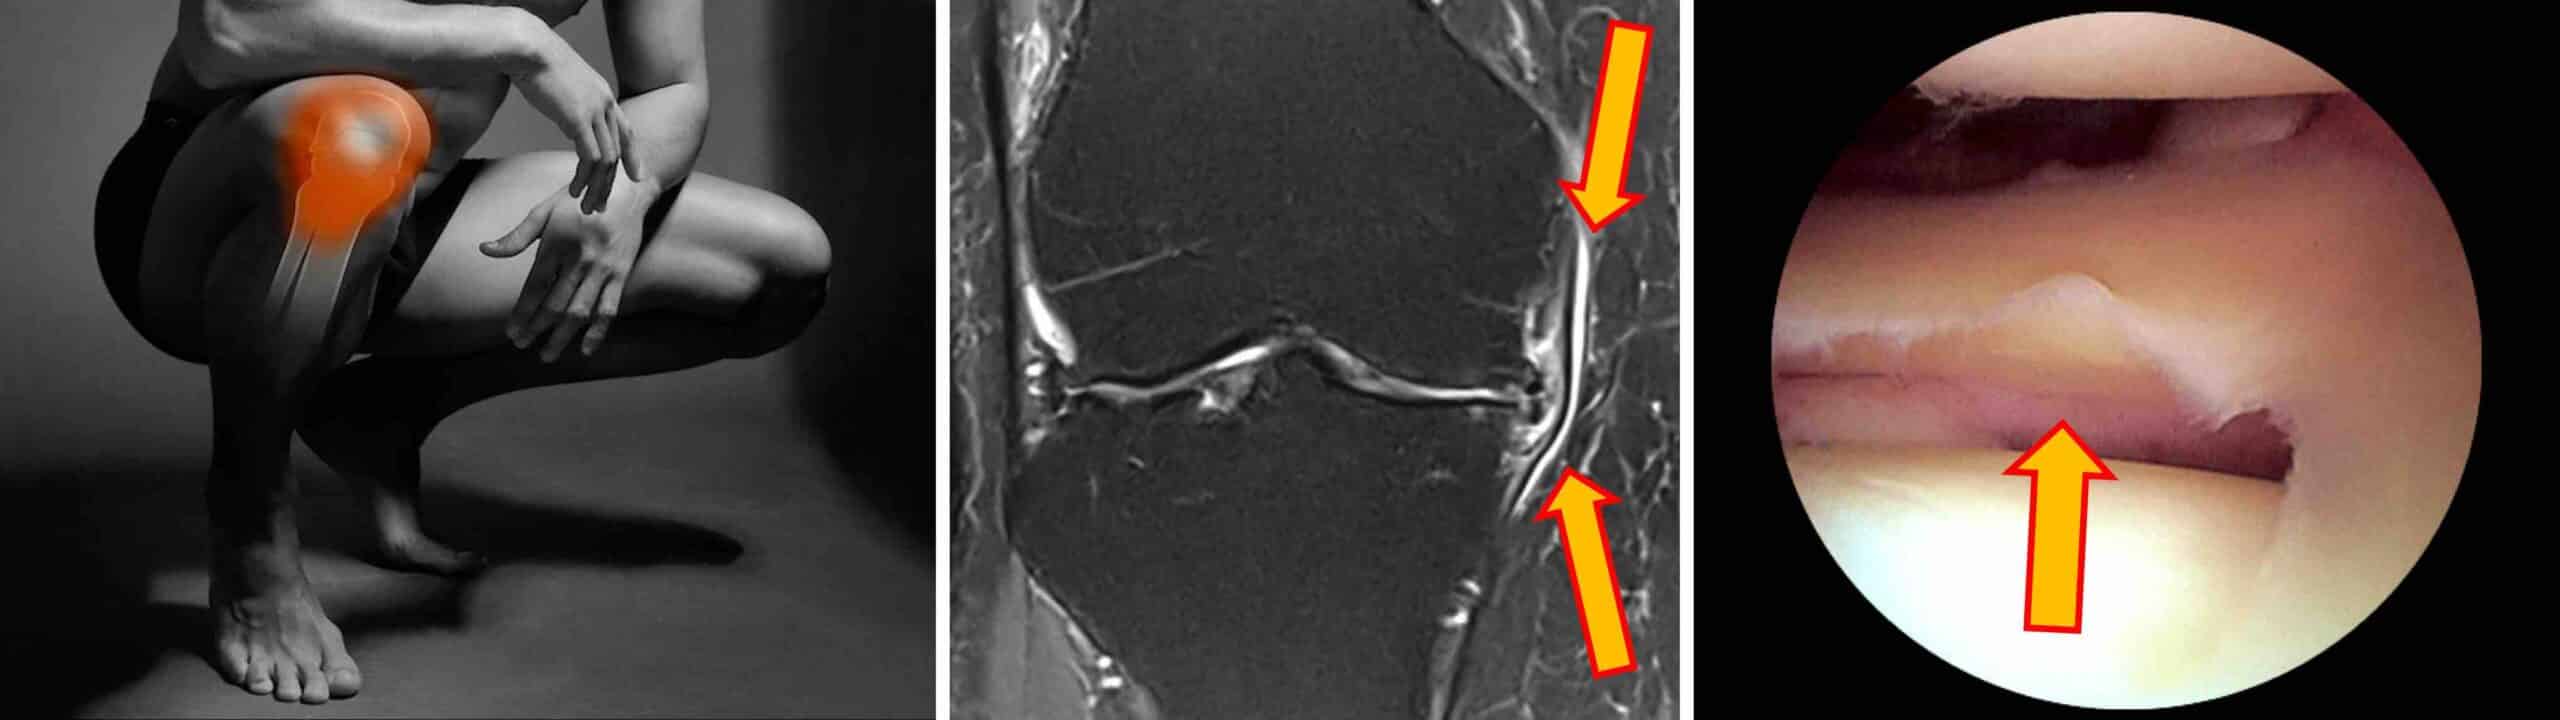

Perimeniscite é o termo médico para o processo inflamatório que ocorre nos tecidos moles ao redor do menisco. O menisco é uma estrutura anatômica formada por fibrocartilagem, com o formato de uma letra C ou meia-lua, que atua como um amortecedor de impactos dentro do joelho. O joelho tem dois meniscos: um medial e outro lateral. Os meniscos estão interpostos entre os côndilos do fêmur e o platô tibial, fazendo a adaptação anatômica entre as superfícies cartilaginosas dos dois ossos. As bordas externas dos meniscos são fixadas à cápsula articular do joelho. A periferia meniscal é ricamente vascularizada e cheia de terminações nervosas. A perimeniscite é o processo inflamatório da periferia meniscal, onde o menisco se conecta à cápsula articular, sendo uma condição bastante dolorosa que sinaliza que algo não está bem na biomecânica do joelho. Uma perimeniscite pode ser identificada no exame de ressonância magnética ou durante uma artroscopia do joelho.

O diagnóstico de perimeniscite é feito pelo exame físico do joelho e confirmado pelo exame de ressonância magnética. Dor à palpação da interlinha articular e manobras positivas para lesão meniscal, como o Teste de McMurray e o Teste de Apley, são achados comuns durante o exame do joelho. Na ressonância magnética a perimeniscite aparece como um edema ou acúmulo de líquido, ou edema, ao redor das bordas do menisco. A perimeniscite pode ser isolada, quando decorrente apenas de uma sobrecarga mecânica, ou associada a uma lesão meniscal ou degeneração articular. Perimeniscites podem também ser diagnosticadas durante uma artroscopia do joelho.